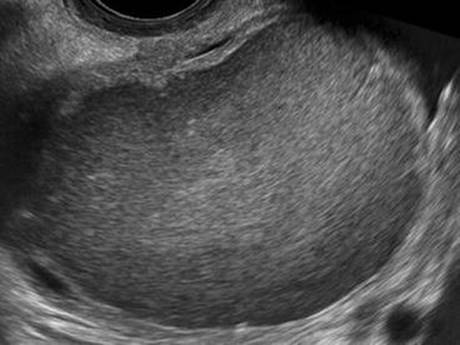

Endometrioma

Physical examination may reveal an adnexal mass; thickened or nodular uterosacral ligaments or rectovaginal septum and a fixed (non-mobile) uterus may also be appreciated, consistent with intraperitoneal scarring due to endometriosis. Transvaginal ultrasound will demonstrate a mass with homogenous “ground-glass” echoes, smooth walls and without internal color Doppler flow (Fig. 4.5); the sensitivity and specificity for the diagnosis of endometrioma by ultrasound is high (77–98 %), but occasionally these can be mistaken for hemorrhagic cysts [56]. Repeat ultrasound should be performed in 6–8 weeks to differentiate an endometrioma from a hemorrhagic cyst, as the latter should resolve [54]. Malignant transformation occurs in 1 % of endometriomas; malignant transformation is more common in endometriomas over 6 cm and in women over 45 years of age [57]. Urgent management is indicated only for evidence of torsion or, rarely, superinfection, which may occur following percutaneous drainage or oocyte retrieval for in vitro fertilization [58]. Please see Chap. 1, Acute Pelvic Pain, for more information on the management of endometriosis; see Chap. 20, Reproductive Endocrinology and Infertility, for management of superinfected endometriomas.

Fig. 4.5

Endometrioma by transvaginal ultrasound (Reprinted from Coccia et al. [74], Figure 3, with kind permission from Springer Science and Business Media)